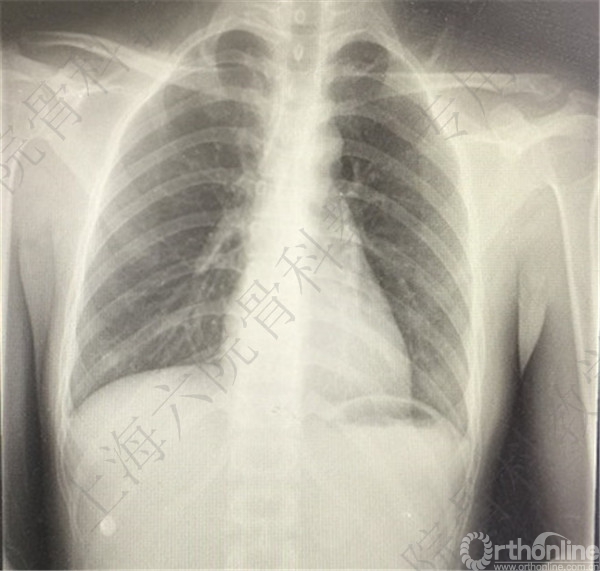

术后X线摄片示:骨折对位对线可。